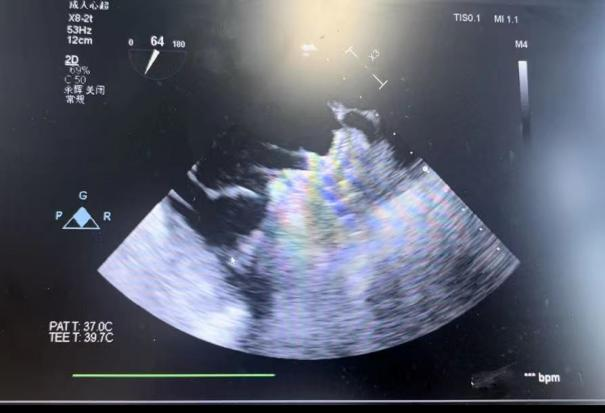

在食道超声引导下进行房间隔穿刺,由于心耳为反鸡翅型,穿刺位点需靠下靠前,潘教授先在90度双腔切面将定位靠下,再在45度主动脉短轴切面将定位靠前。穿刺成功后上导丝交换九州ku酷游LAnavi™分段控弯导引系统送至心耳口部,经过A、B双弯的调整使得鞘管轴向与心耳同轴,获得理想封堵位置。然后推送钢缆释放出固定盘,锚定后退鞘释放出封堵盘。超声下观察贴合良好,无明显残余分流,牵拉测试稳定,即释放左心耳封堵器。释放后再次通过超声各个角度进行验证,封堵结果完美有效,整个过程一气呵成,手术取得了极大的成功。

牵拉测试稳定 完美有效封堵